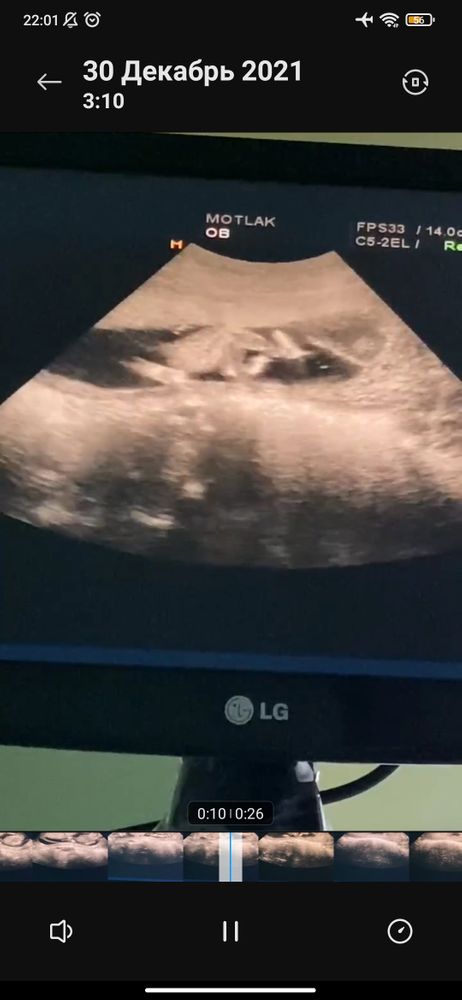

Кто разбирается в УЗИ? Девочки ?

Многоплодная беременность

Это фото слева которая. У второго ребенка я не знаю где она разглядела "возможную девочку" мое любопытство и интерес не даёт мне покоя. Сколько искала в гугле, так и не поняла как выглядят ПО не с бокового ракурса, а как у меня, лицом к нам